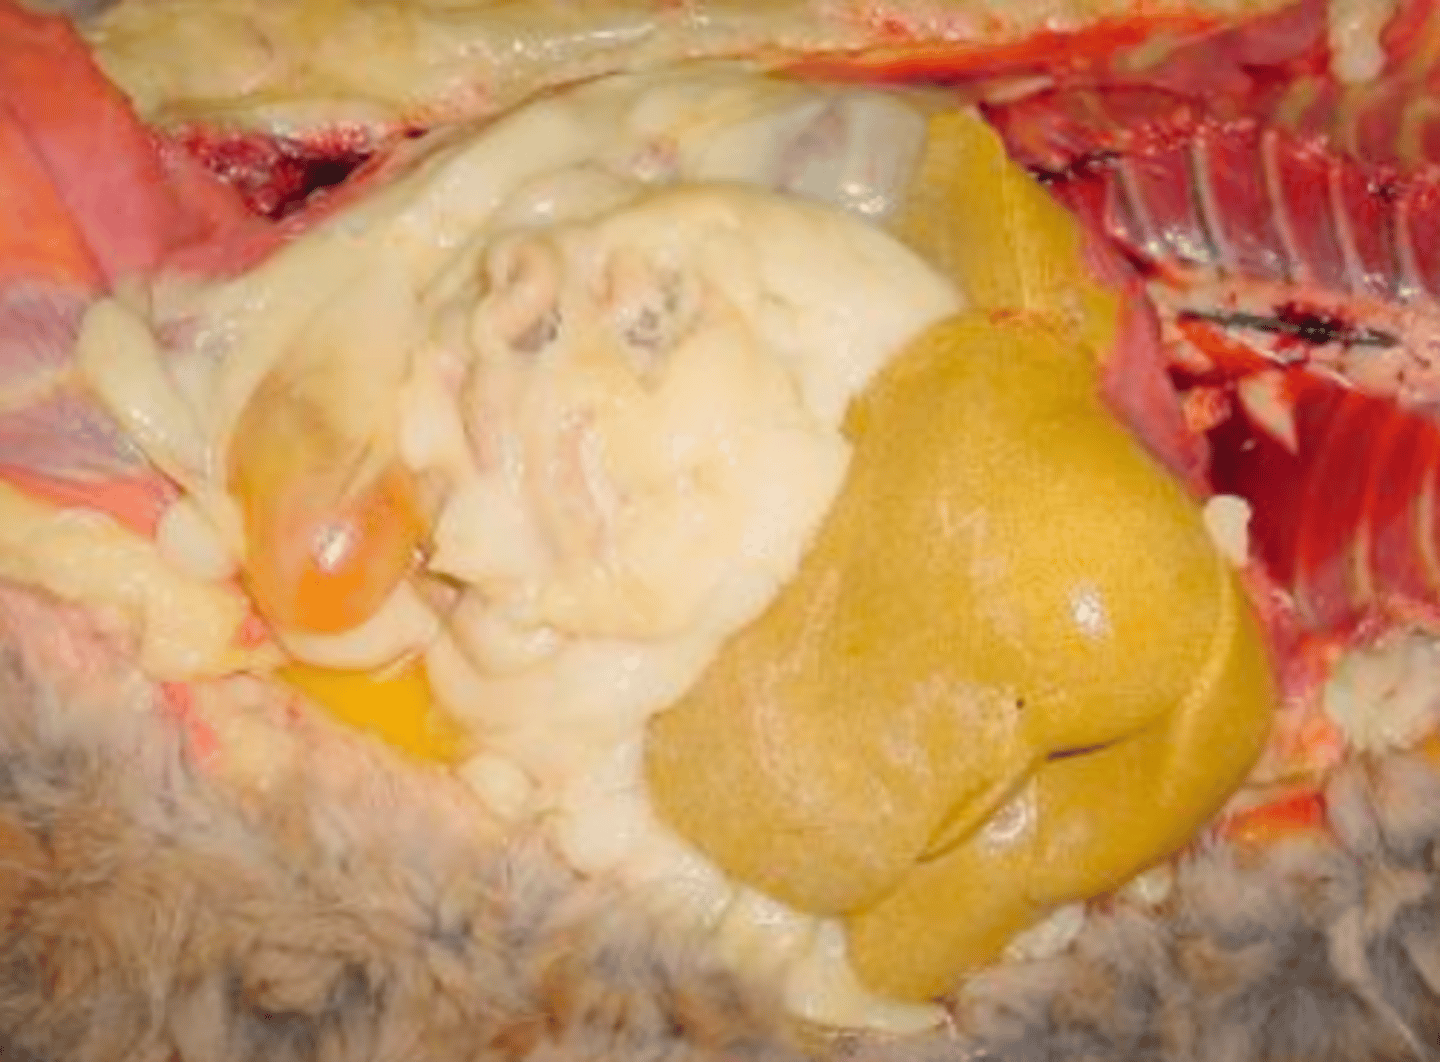

hepatocellular vacuolar change - glycogen type (glycogen in cytoplasm)

Both of these images are showing what?